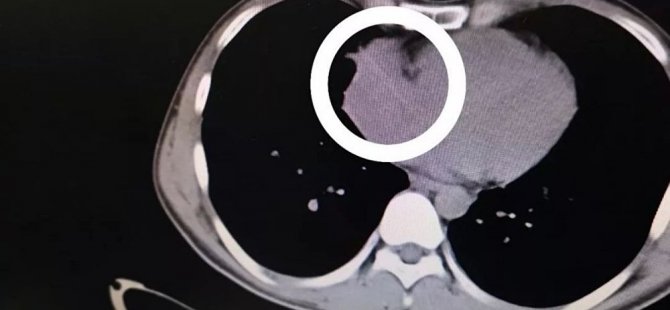

Çin'de doktorlar bir hastanın kalp atışlarındaki dengesizliği araştırırken, tesadüf eseri sağ kalp kapakçığında sivri uçlu bir nesne tespit etti.

Doktorlar, 29 yaşındaki Zhou soyadlı hastanın kalbinin sağ kapakçığında 6 santim uzunluğunda bir kürdan bulduklarını açıkladı. Kürdanın hastanın nefes yolundan geçip sağ ciğerini delerek, kalbe ulaştığı düşünülüyordu. Yedi saatlik bir operasyonun ardından hastanın durumu kontrol altına alındı.

Tetkiklerin ardından doktorlar, Zhou'nun sağ ciğerinde anormal bir gölge ve sağ kalp kapakçığında aşırı bir genişleme tespit ettiler. Genişlemeyi önlemek üzere açık kalp ameliyatına başladıklarında ise, onları kalbe saplanmış bir kürdan karşıladı.